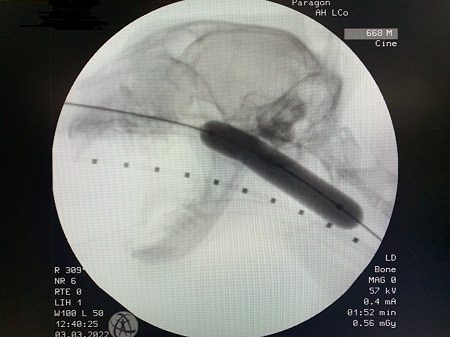

Internal medicine specialist and head of service Andrea Holmes; internal medicine specialist Lizzy Conway and internal medicine intern Simona Borgonovi performed a balloon dilation under fluoroscopy and endoscopy guidance to cure the issue.

Simona said: “The procedure involved the use of an inflatable balloon which was progressively dilated to breakdown the stenosis and help Rupert to be able to breathe silently again.